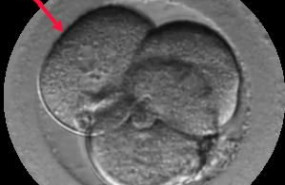

Institut Marquès presenta en el 36º Congreso de la Sociedad Española de Ginecología (SEGO) un estudio sobre la capacidad de auto-reparación de los embriones desde el segundo día tras la fecundación.